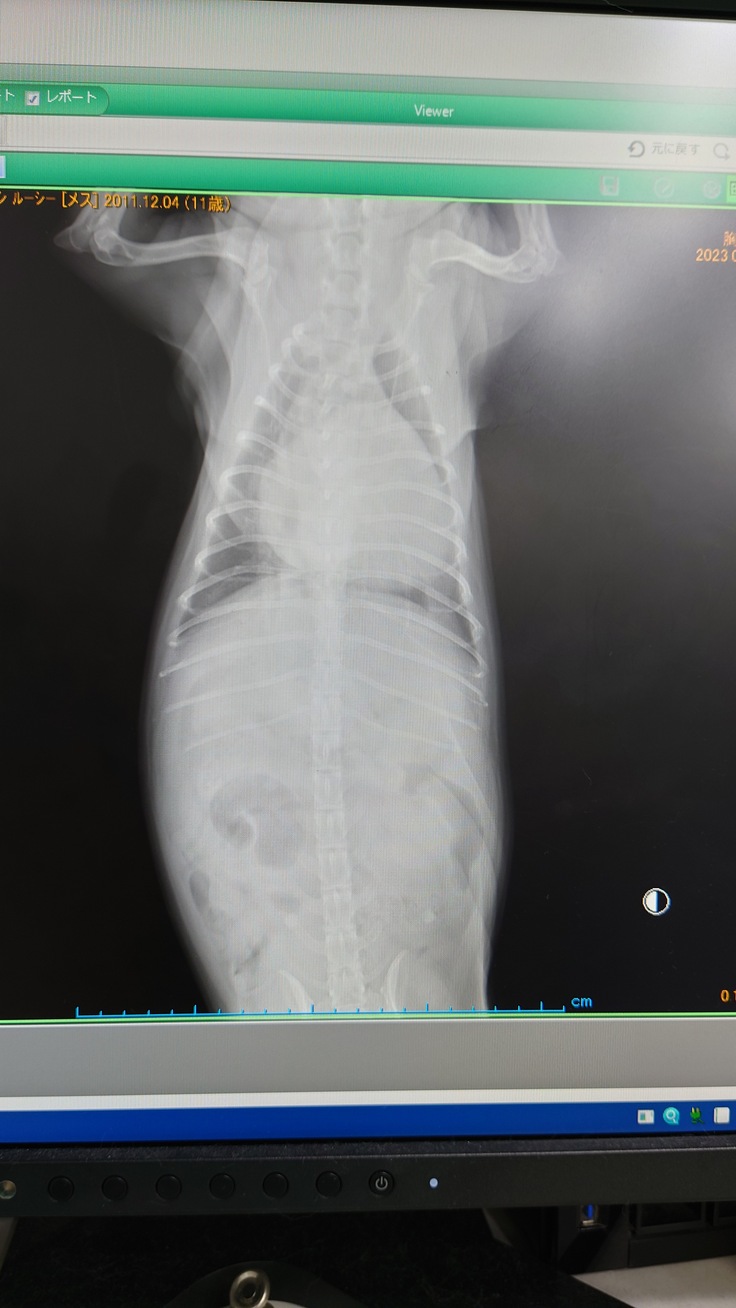

すぐにレントゲンを撮って肺の状態を確認しました。

五日前のレントゲンよりも肺の水の量が増してしまっていたようで

呼吸が荒くなっていたようです。

ギリギリ肺水腫にならなかった、状態とのことだそうです。

利尿剤の量が4分の1日2回から、2分の1を1日2回へ変更、

ピンク色の薬、ピモベハートも1日半分を1日2回から、1個を一日2回に変更となり、

薬の投薬量が2倍になりました。

腎臓が強い、というのが処方の根拠だとは思います。